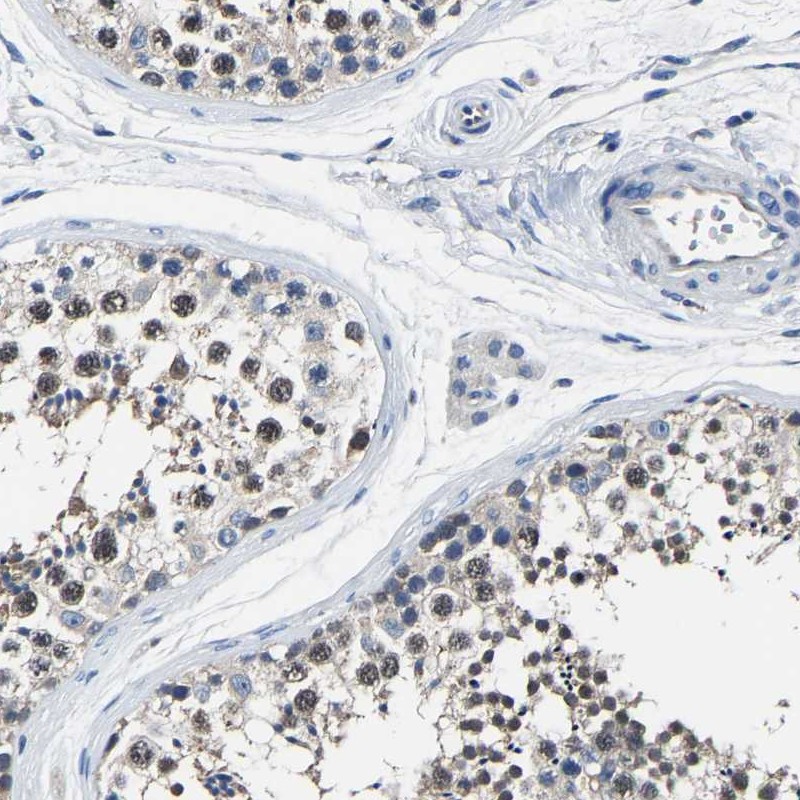

Immunohistochemical staining of human testis shows moderate nuclear positivity in cells in seminiferus ducts.